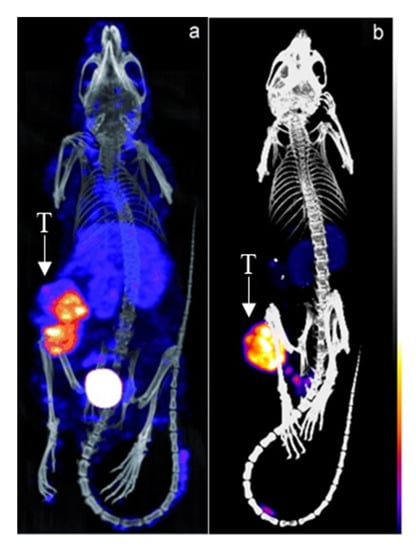

- Cheal, S.M.; Xu, H.; Guo, H.f.; Lee, S.g.; Punzalan, B.; Chalasani, S.; Fung, E.K.; Jungbluth, A.; Zanzonico, P.B.; Carrasquillo, J.A.; et al. Theranostic Pretargeted Radioimmunotherapy of Colorectal Cancer Xenografts in Mice Using Picomolar Affinity 86Y- or 177Lu-DOTA-Bn Binding ScFv C825/GPA33 IgG Bispecific Immunoconjugates. Eur. J. Nucl. Med. Mol. Imaging 2016, 43, 925–937. [Google Scholar] [CrossRef]

- Cheal, S.M.; Xu, H.; Guo, H.; Patel, M.; Punzalan, B.; Fung, E.K.; Lee, S.; Bell, M.; Singh, M.; Jungbluth, A.A.; et al. Theranostic Pretargeted Radioimmunotherapy of Internalizing Solid Tumor Antigens in Human Tumor Xenografts in Mice: Curative Treatment of HER2-Positive Breast Carcinoma. Theranostics 2018, 8, 5106–5125. [Google Scholar] [CrossRef]

- Cheal, S.M.; Yoo, B.; Boughdad, S.; Punzalan, B.; Yang, G.; Dilhas, A.; Torchon, G.; Pu, J.; Axworthy, D.B.; Zanzonico, P.; et al. Evaluation of Glycodendron and Synthetically Modified Dextran Clearing Agents for Multistep Targeting of Radioisotopes for Molecular Imaging and Radioimmunotherapy. Mol. Pharm. 2014, 11, 400–416. [Google Scholar] [CrossRef]